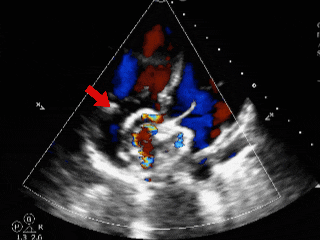

锁定后评估

心尖四腔心切面可见封堵器形态良好

主动脉短轴切面可见封堵器呈“Y”字型抱住主动脉

彩色多普勒血流成像显示无残余分流存在

释放后评估

封堵器位置正确、形态良好

封堵成功